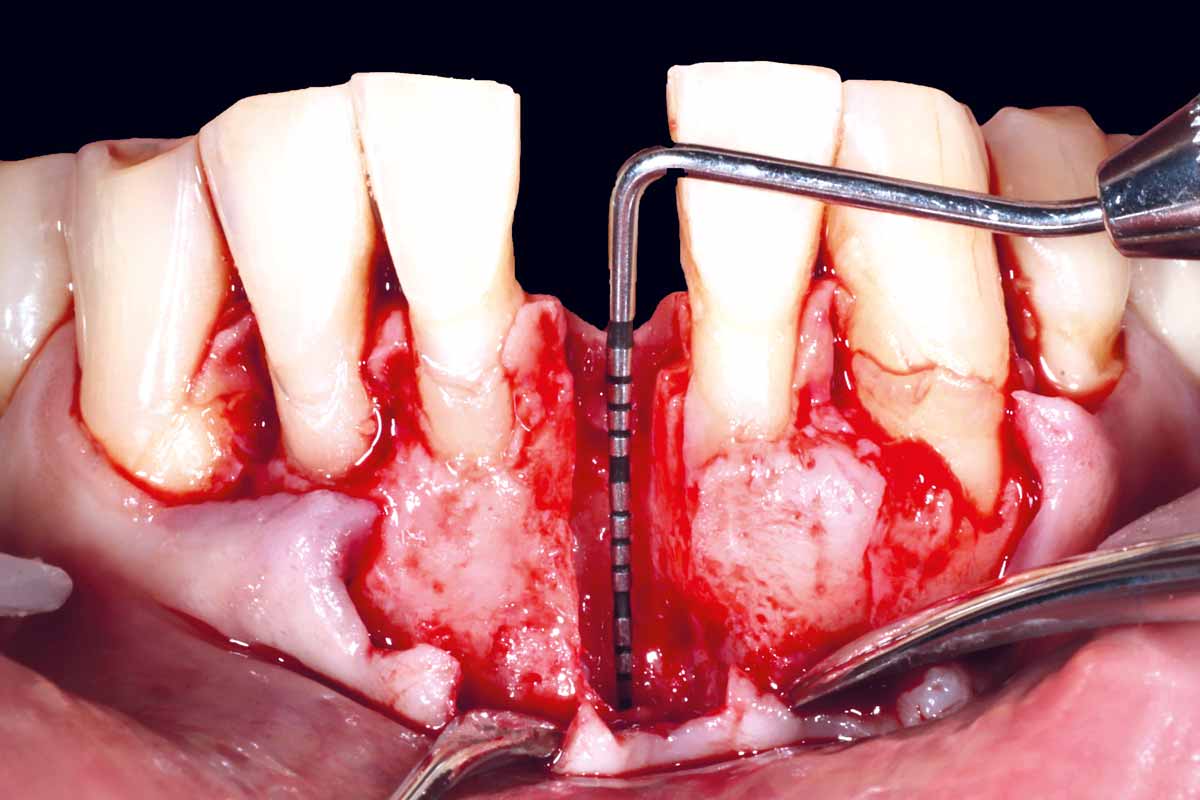

Bone regeneration and implant-supported rehabilitation of a periodontally involved incisor - Dr. A. Eslava Vanegas

47 years old patient referred by another dentist after suffering a fall while fishing